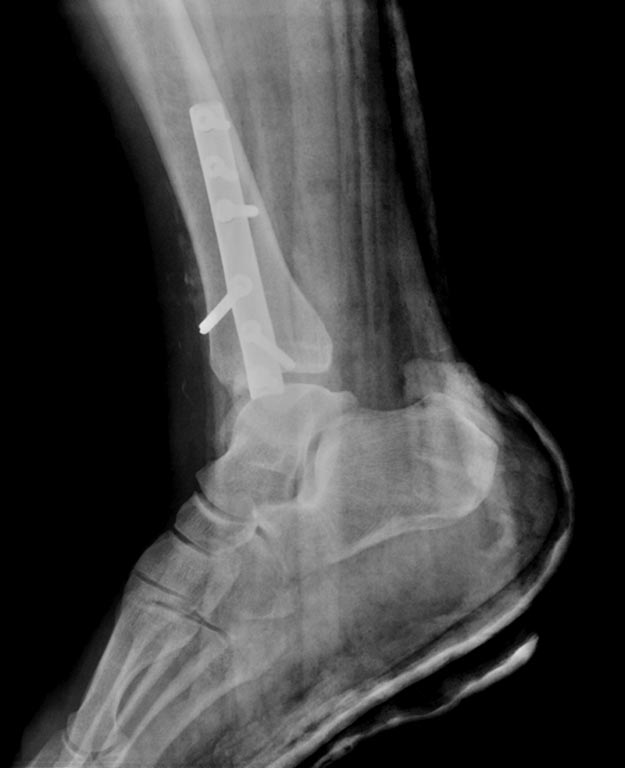

[Ortho] сохраняется подвывих?

длиннее пластины нет (скоро никаких не будет), ехать в другие учреждения

пациент отказался. после операции прошло 3 дня, от момента травмы -

неделя. пациент ходит в гипсе без нагрузки на ногу. интересует, что

делать сейчас.

Имя     : 4 РПУМЕ ПРЕТБГИ?И?2.jpg